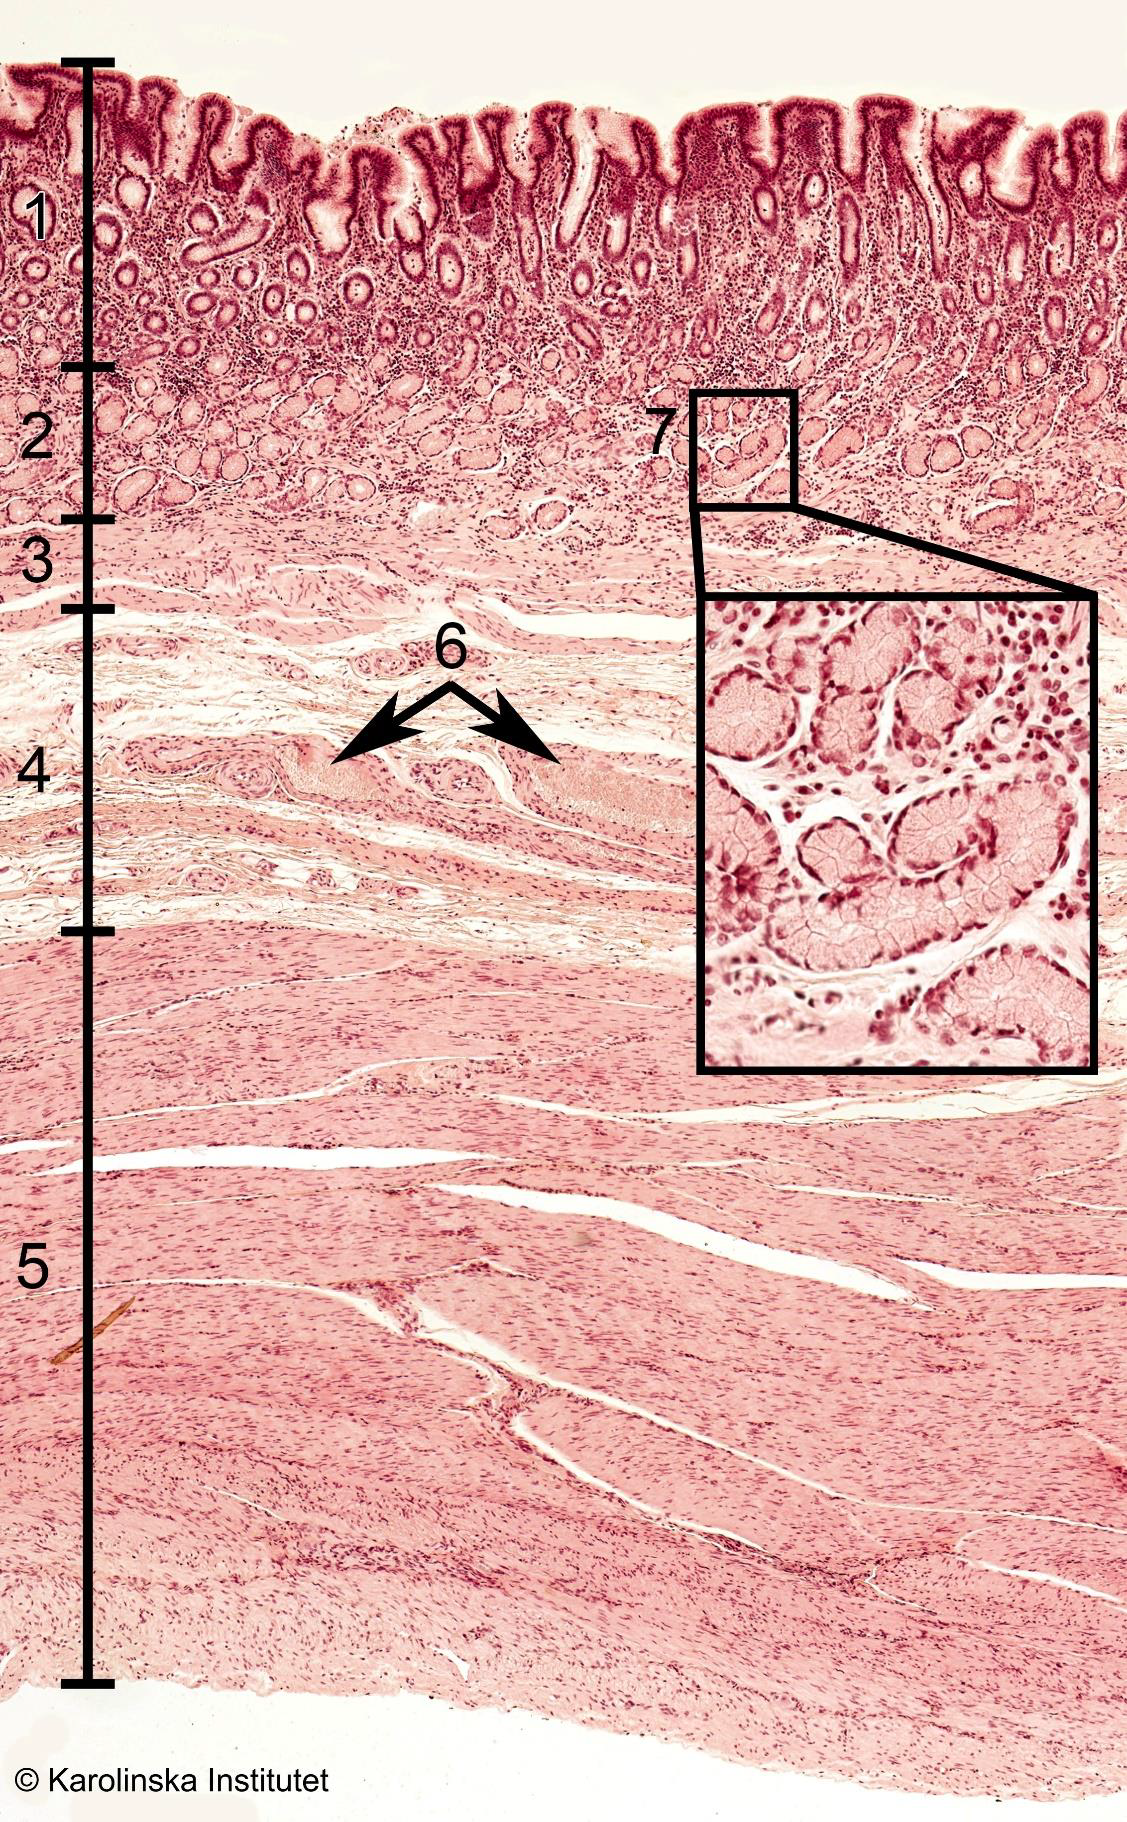

Duodenum

1

2

3

41. Villi (cross-cut),

2. Lamina propria,

3. Glands,

4. GlandsIleum

4

5

6

72. Villi,

3. Mucosa,

4. Submucosa,

5. Muscularis,

6. Muscularis,

7. Serosa,

8. Paneth cellsColon